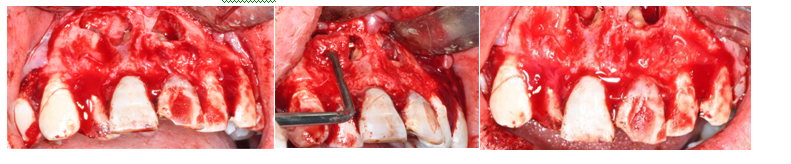

骨增量技术:对于牙槽骨骨量不足的患者,采用骨增量技术来增加骨量,以满足种植牙等手术的需求。常见的骨增量技术包括引导骨组织再生术(GBR)、上颌窦提升术、骨劈开术等。这些技术通过使用生物材料和特殊的手术方法,促进牙槽骨的再生和修复,扩大了种植牙的适应证,使更多患者能够接受种植修复。

牙槽根尖外科:借助牙科显微镜的放大和照明功能,在直视下对根尖周病变进行精确诊断和治疗的口腔外科手术方法。通过手术切除根尖病变组织,对根尖进行处理和倒充填,以消除根尖周炎症,促进病变愈合,最大程度保留患牙及其功能。